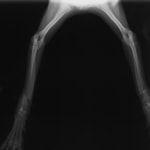

骨盤骨折 : 症例1 | 症例2 | 症例3 | 症例4

症例3:キルシュナーワイヤーのピンニングによる整復

ペルシャ猫 11ヶ月齢 雄

他院にて左大腿骨遠位の成長板骨折(salter-harrisⅠ型)が認められており、治療相談を目的として来院。当院にて、キルシュナーワイヤーを用いたピンニングにより骨折部位の整復を行いました。術後の経過は良好で、現在も経過観察中です。

術前レントゲン

術後レントゲン